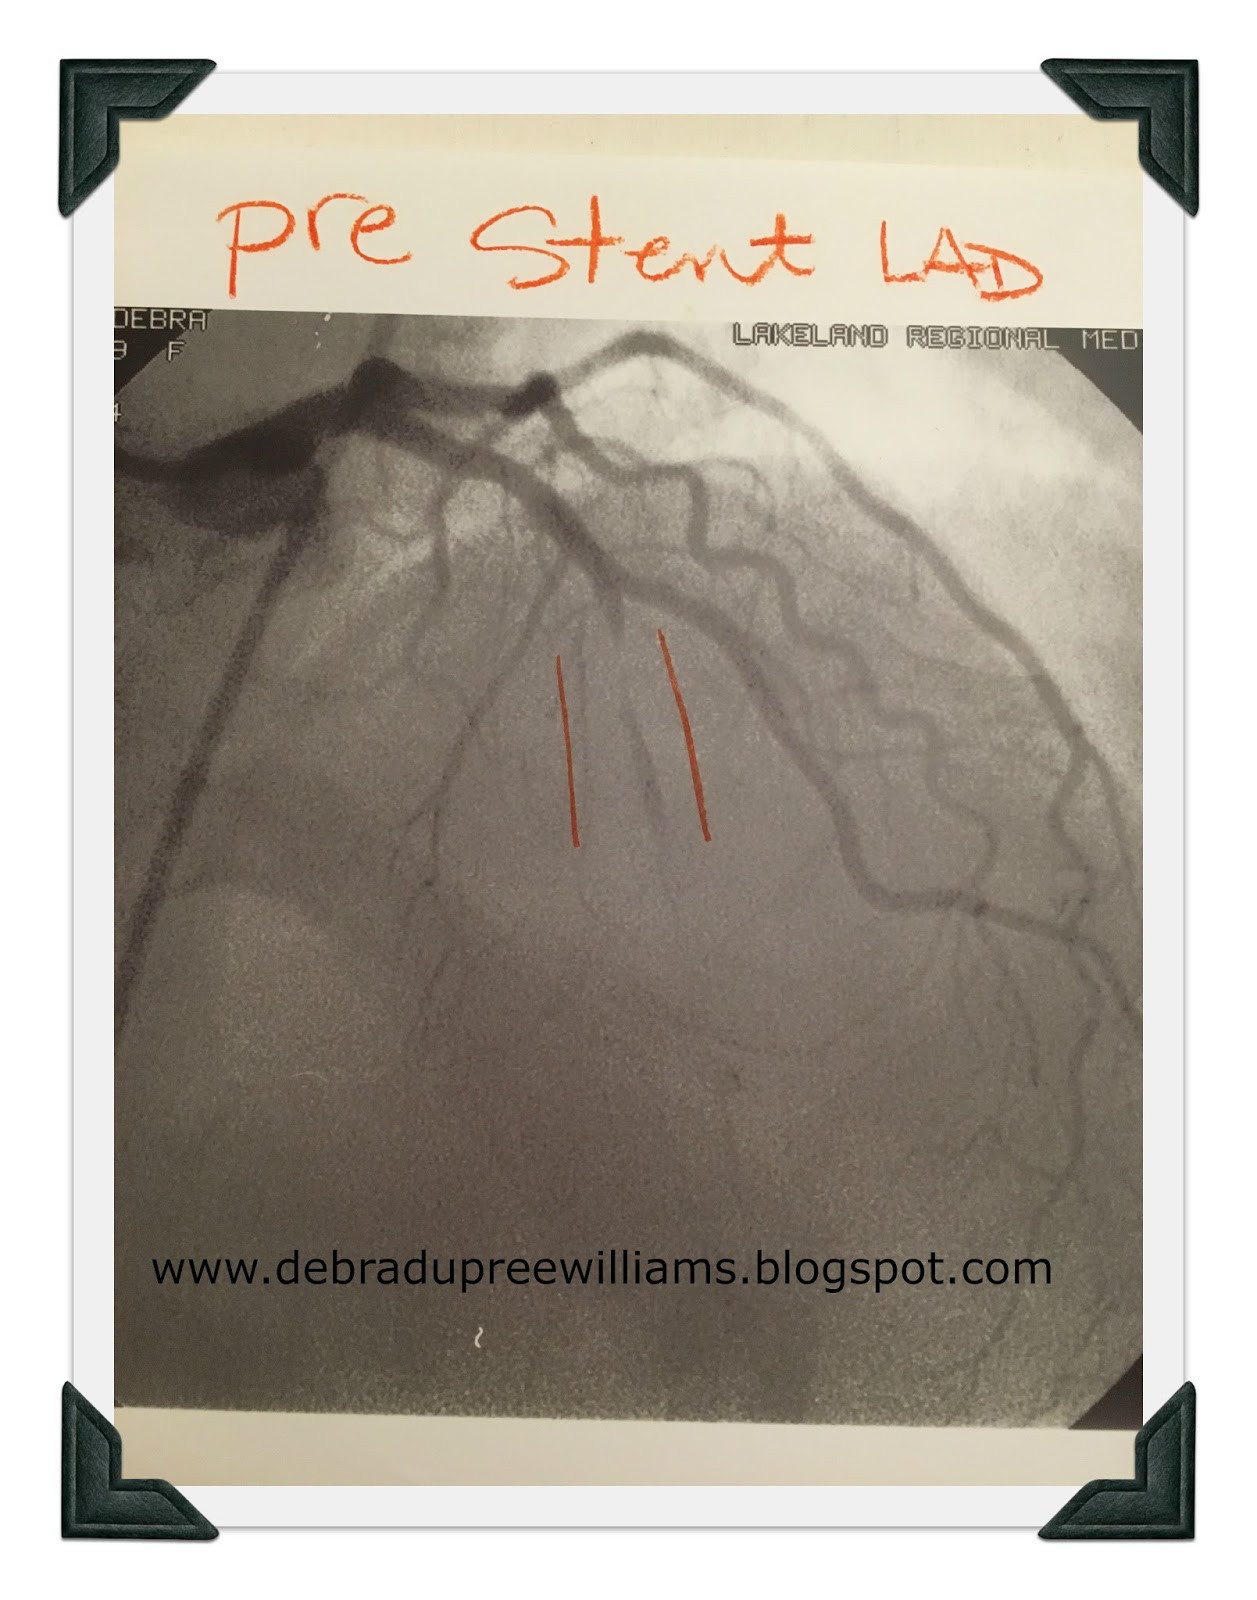

After I had received the stent and recovered sufficiently for the doctor to talk to us, he showed us before and after x-rays. By the grace of God alone, I had a tiny little blood vessel that had formed its own bypass around the clogged artery, the main one on the front of the heart, the Left Anterior Descending, the LAD, also known as the widow-maker. It was 99.9% blocked. But I was still alive!